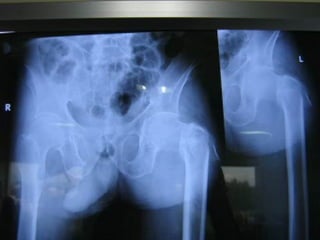

1. Hip replacement

2. Knee replacement

3. Shoulder replacement

4. Elbow replacement

   Total knee replacement (TKR)

and hip fracture coming for

replacement are the two most

common surgical procedures

after the sixth decade of life.